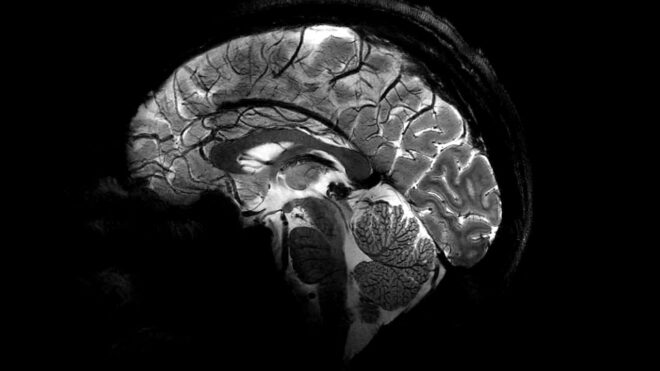

Fransa Alternatif Enerjiler ve Atom Enerjisi Komisyonu (CEA) tarafından geliştirilen Iseult MRI makinesi, aktarıldığı kadarıyla tam 11.7 Teslas (T) gücünde çekim gerçekleştirebiliyor. Söylendiği kadarıyla hastanelerde kullanılan normal MRI makineleri genelde 3 Teslas (T) gücün üstüne çıkmıyor, bu gerçekten çok ciddi güç farkı sayesinde normalden daha yüksek detay alınabiliyor. Yukarıdaki görüntüler de bahsi geçen makine ile kayıt altına alınan ilk insan beyni detaylarını karşımıza getiriyor. Bizim farkı anlamamız elbette çok zor ancak görsellerde doktorların normalde görmediği inanılmaz detayların olduğu, bu detayların beynin nasıl çalıştığını daha iyi anlamamıza ve nörodejeneratif hastalıkları (Alzheimer ve Parkinson gibi) daha iyi şekilde tedavi etmemize yardımcı olacağı söyleniyor. Normal MRI sistemleriyle böyle detaylı görüntülerin alınması için bir hastanın tam iki saat boyunca yatarak hareketsiz kalması gerekirken, “Iseult” ile sonuç sadece dört dakikada alınabiliyor. Gücüne bağlı olarak çok büyük olduğu aktarılan 132 tonluk makinenin, içindeki mıknatısları soğutmak için tam 7.500 litre sıvı helyum kullandığı aktarılıyor.